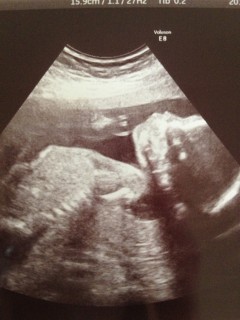

22W2D 539gでした。

アイーンをしています。

結構沢山動いていました♪

性別を聞いたところ

90%女の子と言われました☆